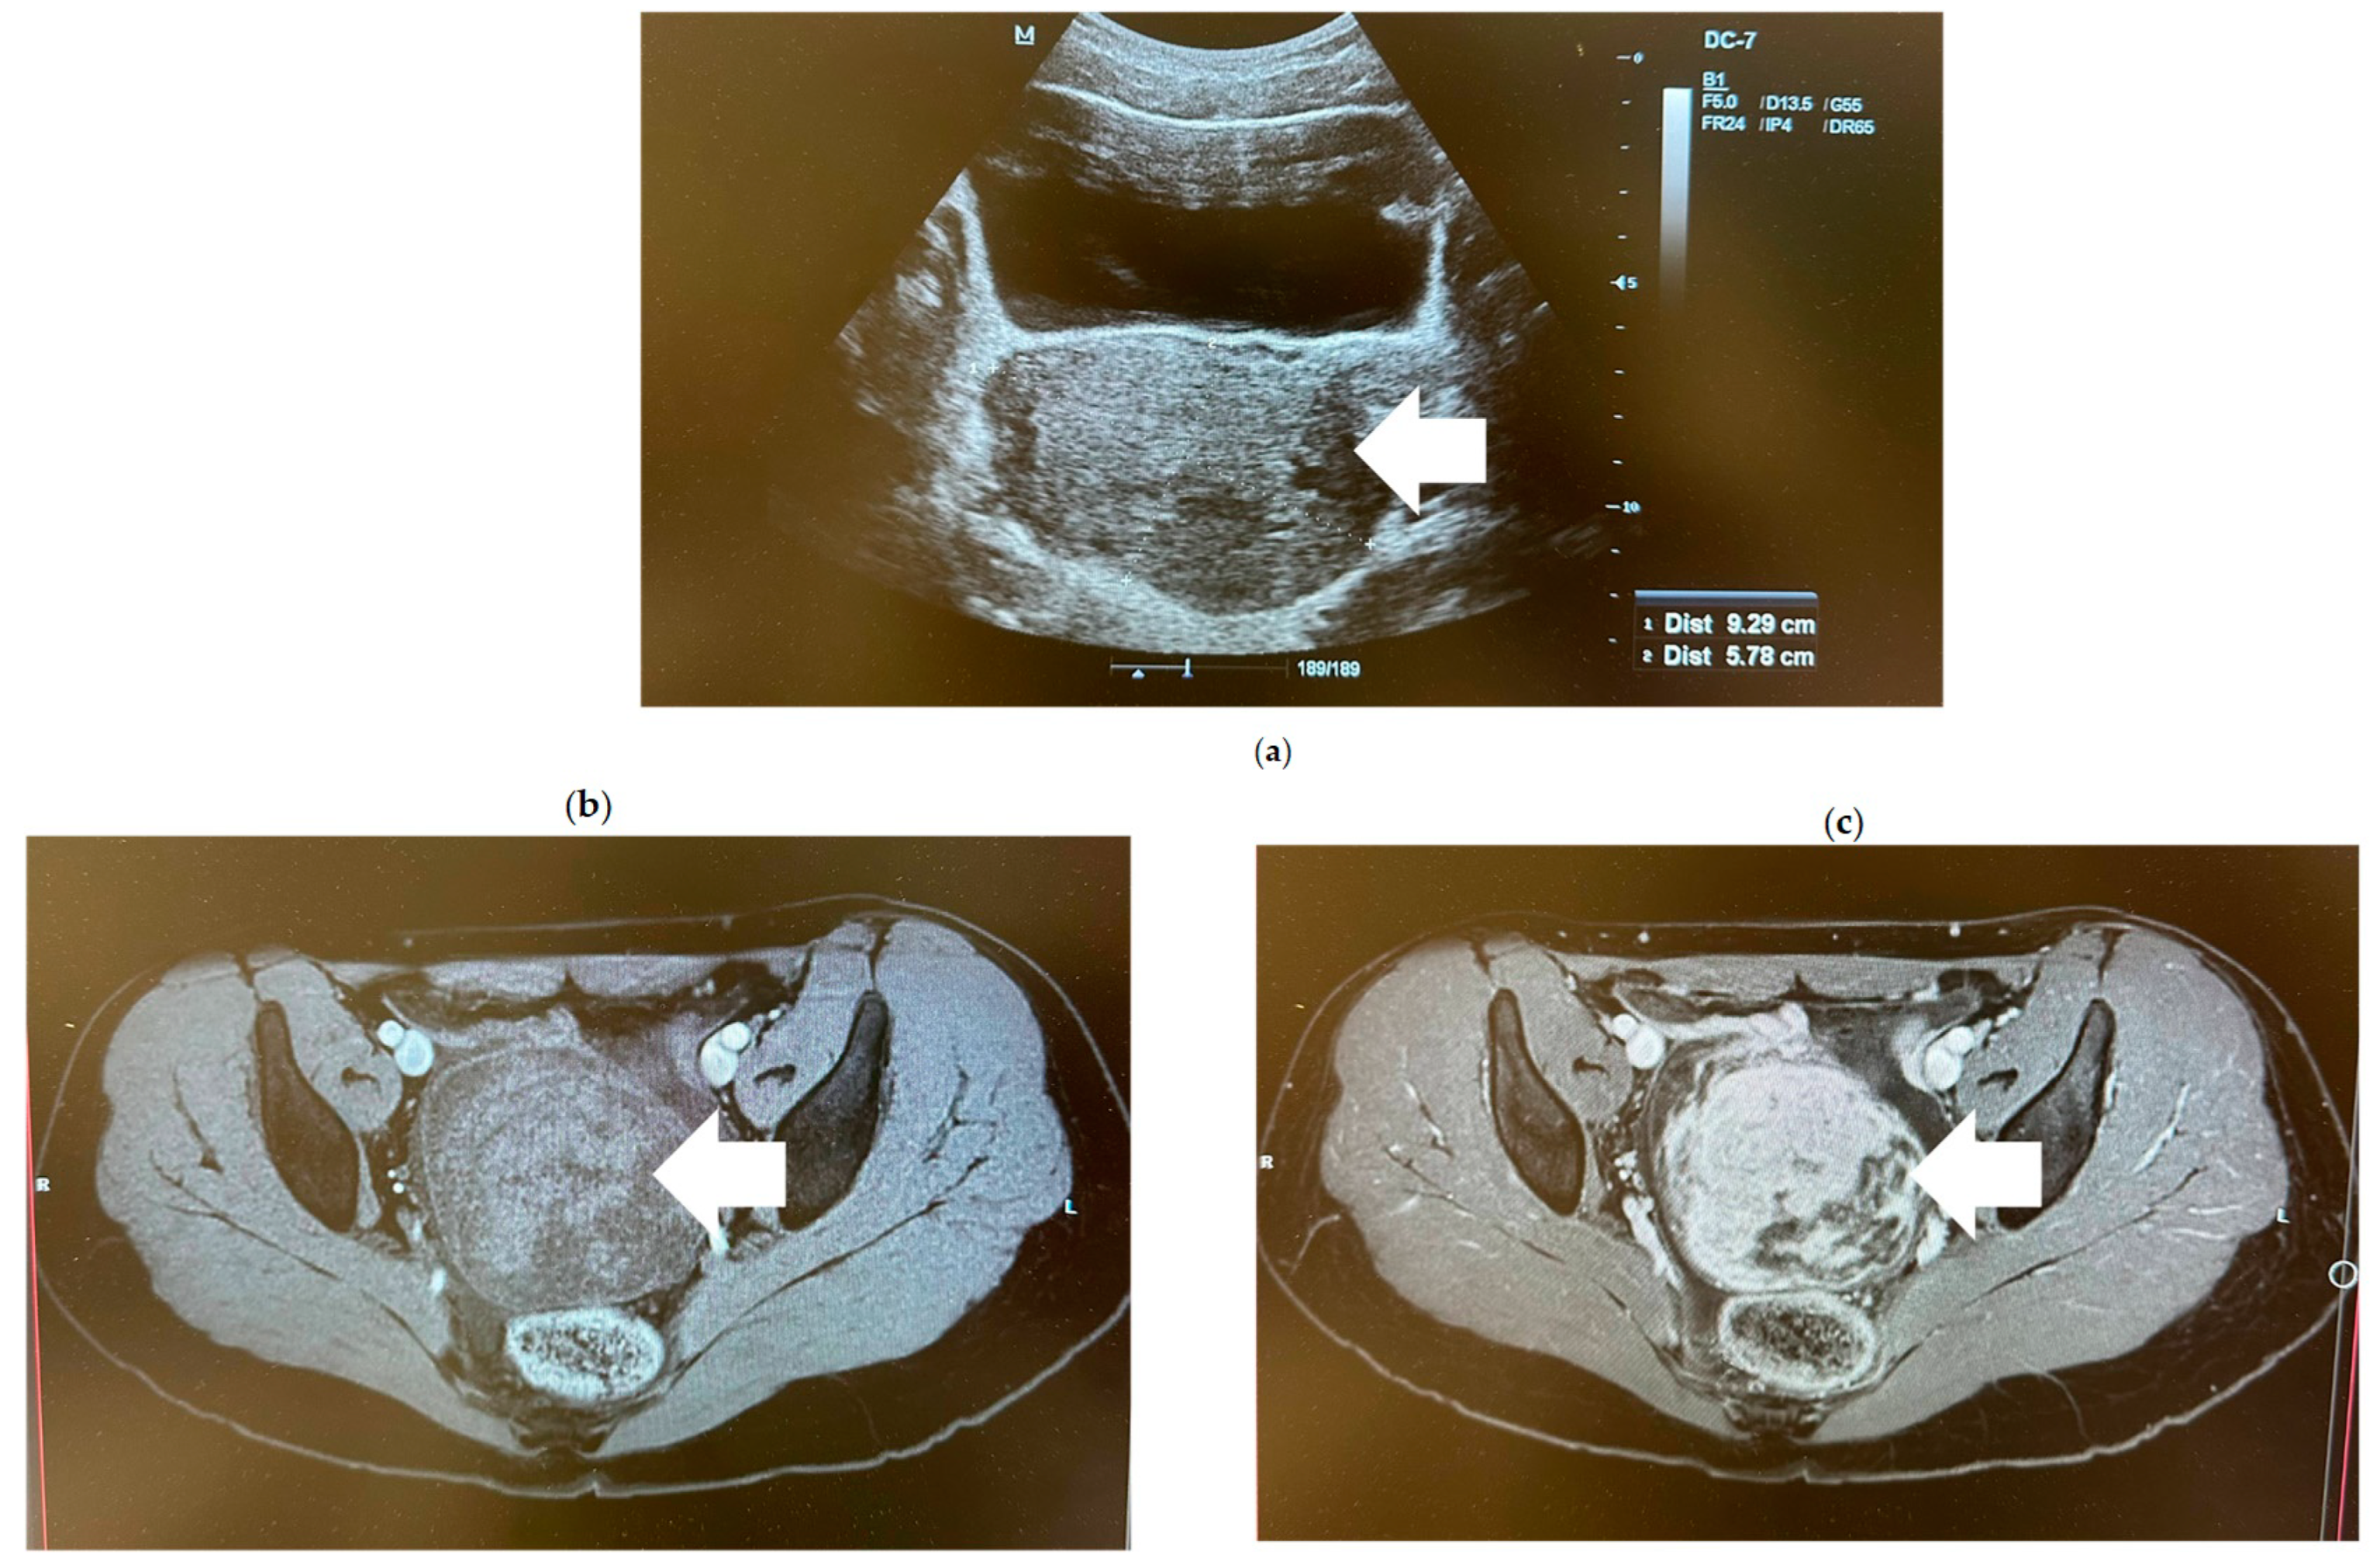

2. Case Report